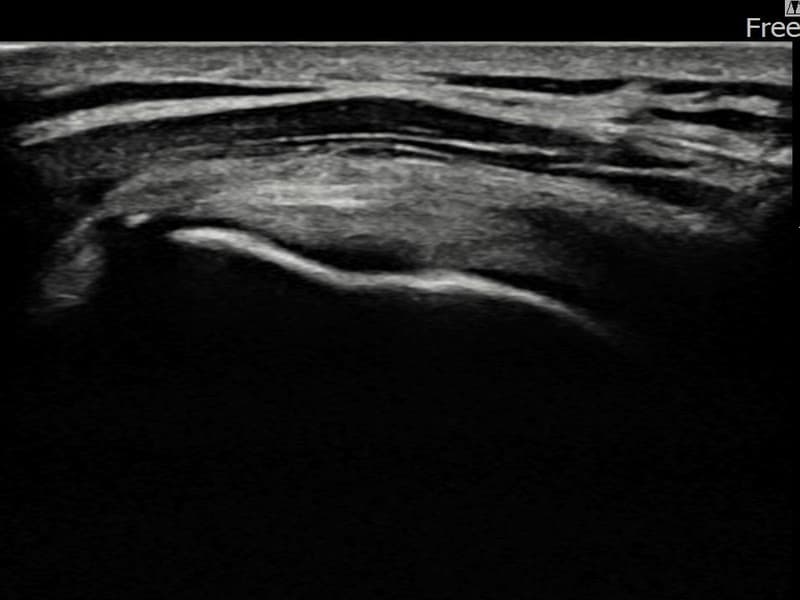

After

시술 전 초음파 측정 결과 파열 크기는 7mm × 3mm (힘줄 두께의 약 30% 결손)로 확인되었습니다. 시술 전 초음파에서 좌측 극상근건 내 에코 단절과 힘줄 결손 소견이 확인되었습니다. 시술 후 8개월 추적 초음파에서 파열 부위에 재생 조직이 완전히 채워지고 힘줄 에코 패턴이 정상화된 것이 관찰되었습니다.

50대 중반 남성 환자분으로, 좌측 어깨 통증이 오래 지속되었으나 바쁜 일상으로 치료를 미루시다가 통증이 악화되어 내원하셨습니다. 초음파 검사에서 좌측 극상근건 부분파열이 확인되었으며, 초음파 유도 하 축소봉합술을 시행하였습니다. 이 환자분의 경우 시술 후 8개월 간격의 장기 추적 초음파를 시행하였는데, 파열 부위가 완전히 재생 조직으로 채워지고 힘줄 구조가 정상화된 우수한 결과를 보여주셨습니다. 현재 통증 없이 정상 생활을 하고 계십니다.